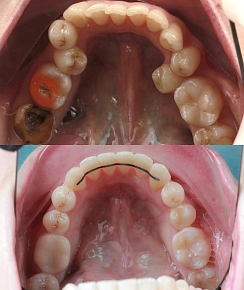

Зуб сильно разрушился, можно ли избежать удаления?